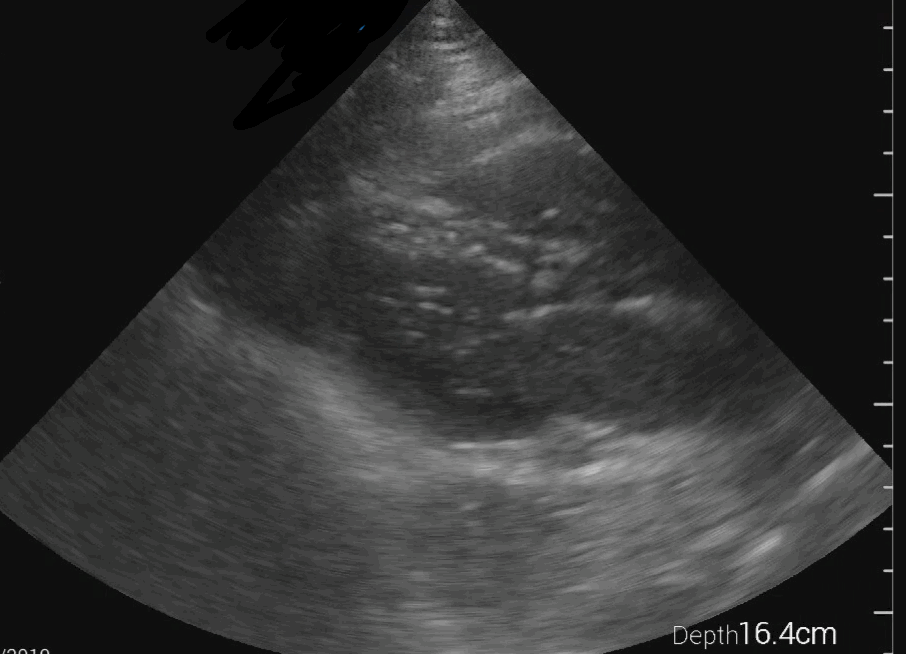

PLAX view

PLAX view of an empty left ventricle with severe hypertrophy: In this PLAX view, the left ventricle appears empty and shows severe hypertrophy. There is some muscular activity visible, suggesting continued cardiac effort, which supports ongoing resuscitation and addressing the potential hypovolemic state. Additionally, a small rim of pericardial effusion is noted, which should be carefully evaluated to determine if emergency drainage is required.